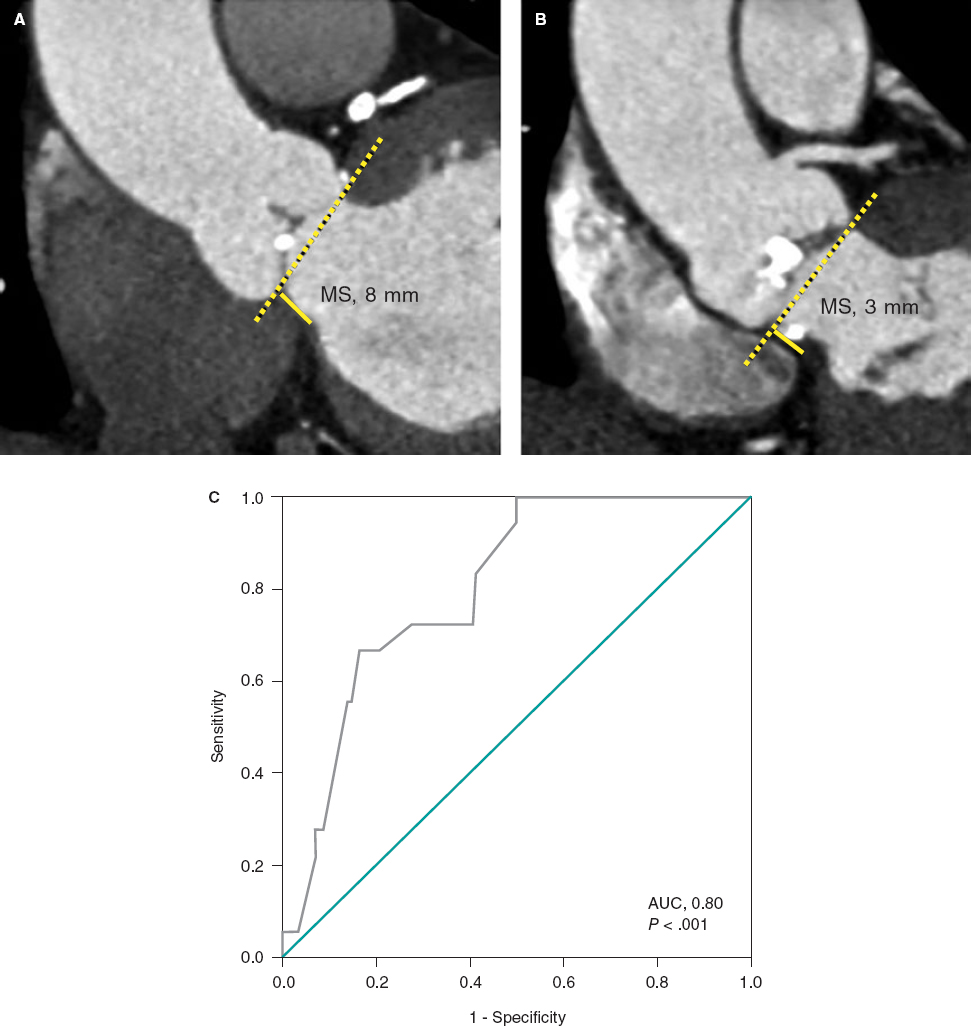

Predilatation occurred in 32 lesions (51.6%) and postdilatation in 37 (59.7%). The criterion used for postdilatation was angiography guided visual underexpansion. Intravascular ultrasound was performed in 15 patients (30%) before the implant. It was also used in 2 patients to optimize the percutaneous coronary intervention given the persistent stent underexpansion seen on the angiography. In both cases the minimum lumen area was > 5.5 mm2 with stent expansion > 80% and lack of incomplete apposition (defined as a strut separation of > 0.4 mm axial and 1 mm longitudinal) (figure 2). The optical coherence tomography was performed in a patient with ST-segment elevation acute coronary syndrome before and after the implant. It revealed a high thrombotic load with lack of immediate stent malapposition.

Figure 2. A: acute thrombotic occlusion in left circumflex artery with Thrombolysis in Myocardial Infarction flow grade 0. B: the intravascular ultrasound shows a great deal of thrombus in the lesions despite thrombus aspiration. C: implantation of 2 3.5-4.5 mm × 27 mm Xposition S overlapping stents. D: the intravascular ultrasound performed after stent implantation confirms the good angiographic results and lack of stent malapposition.